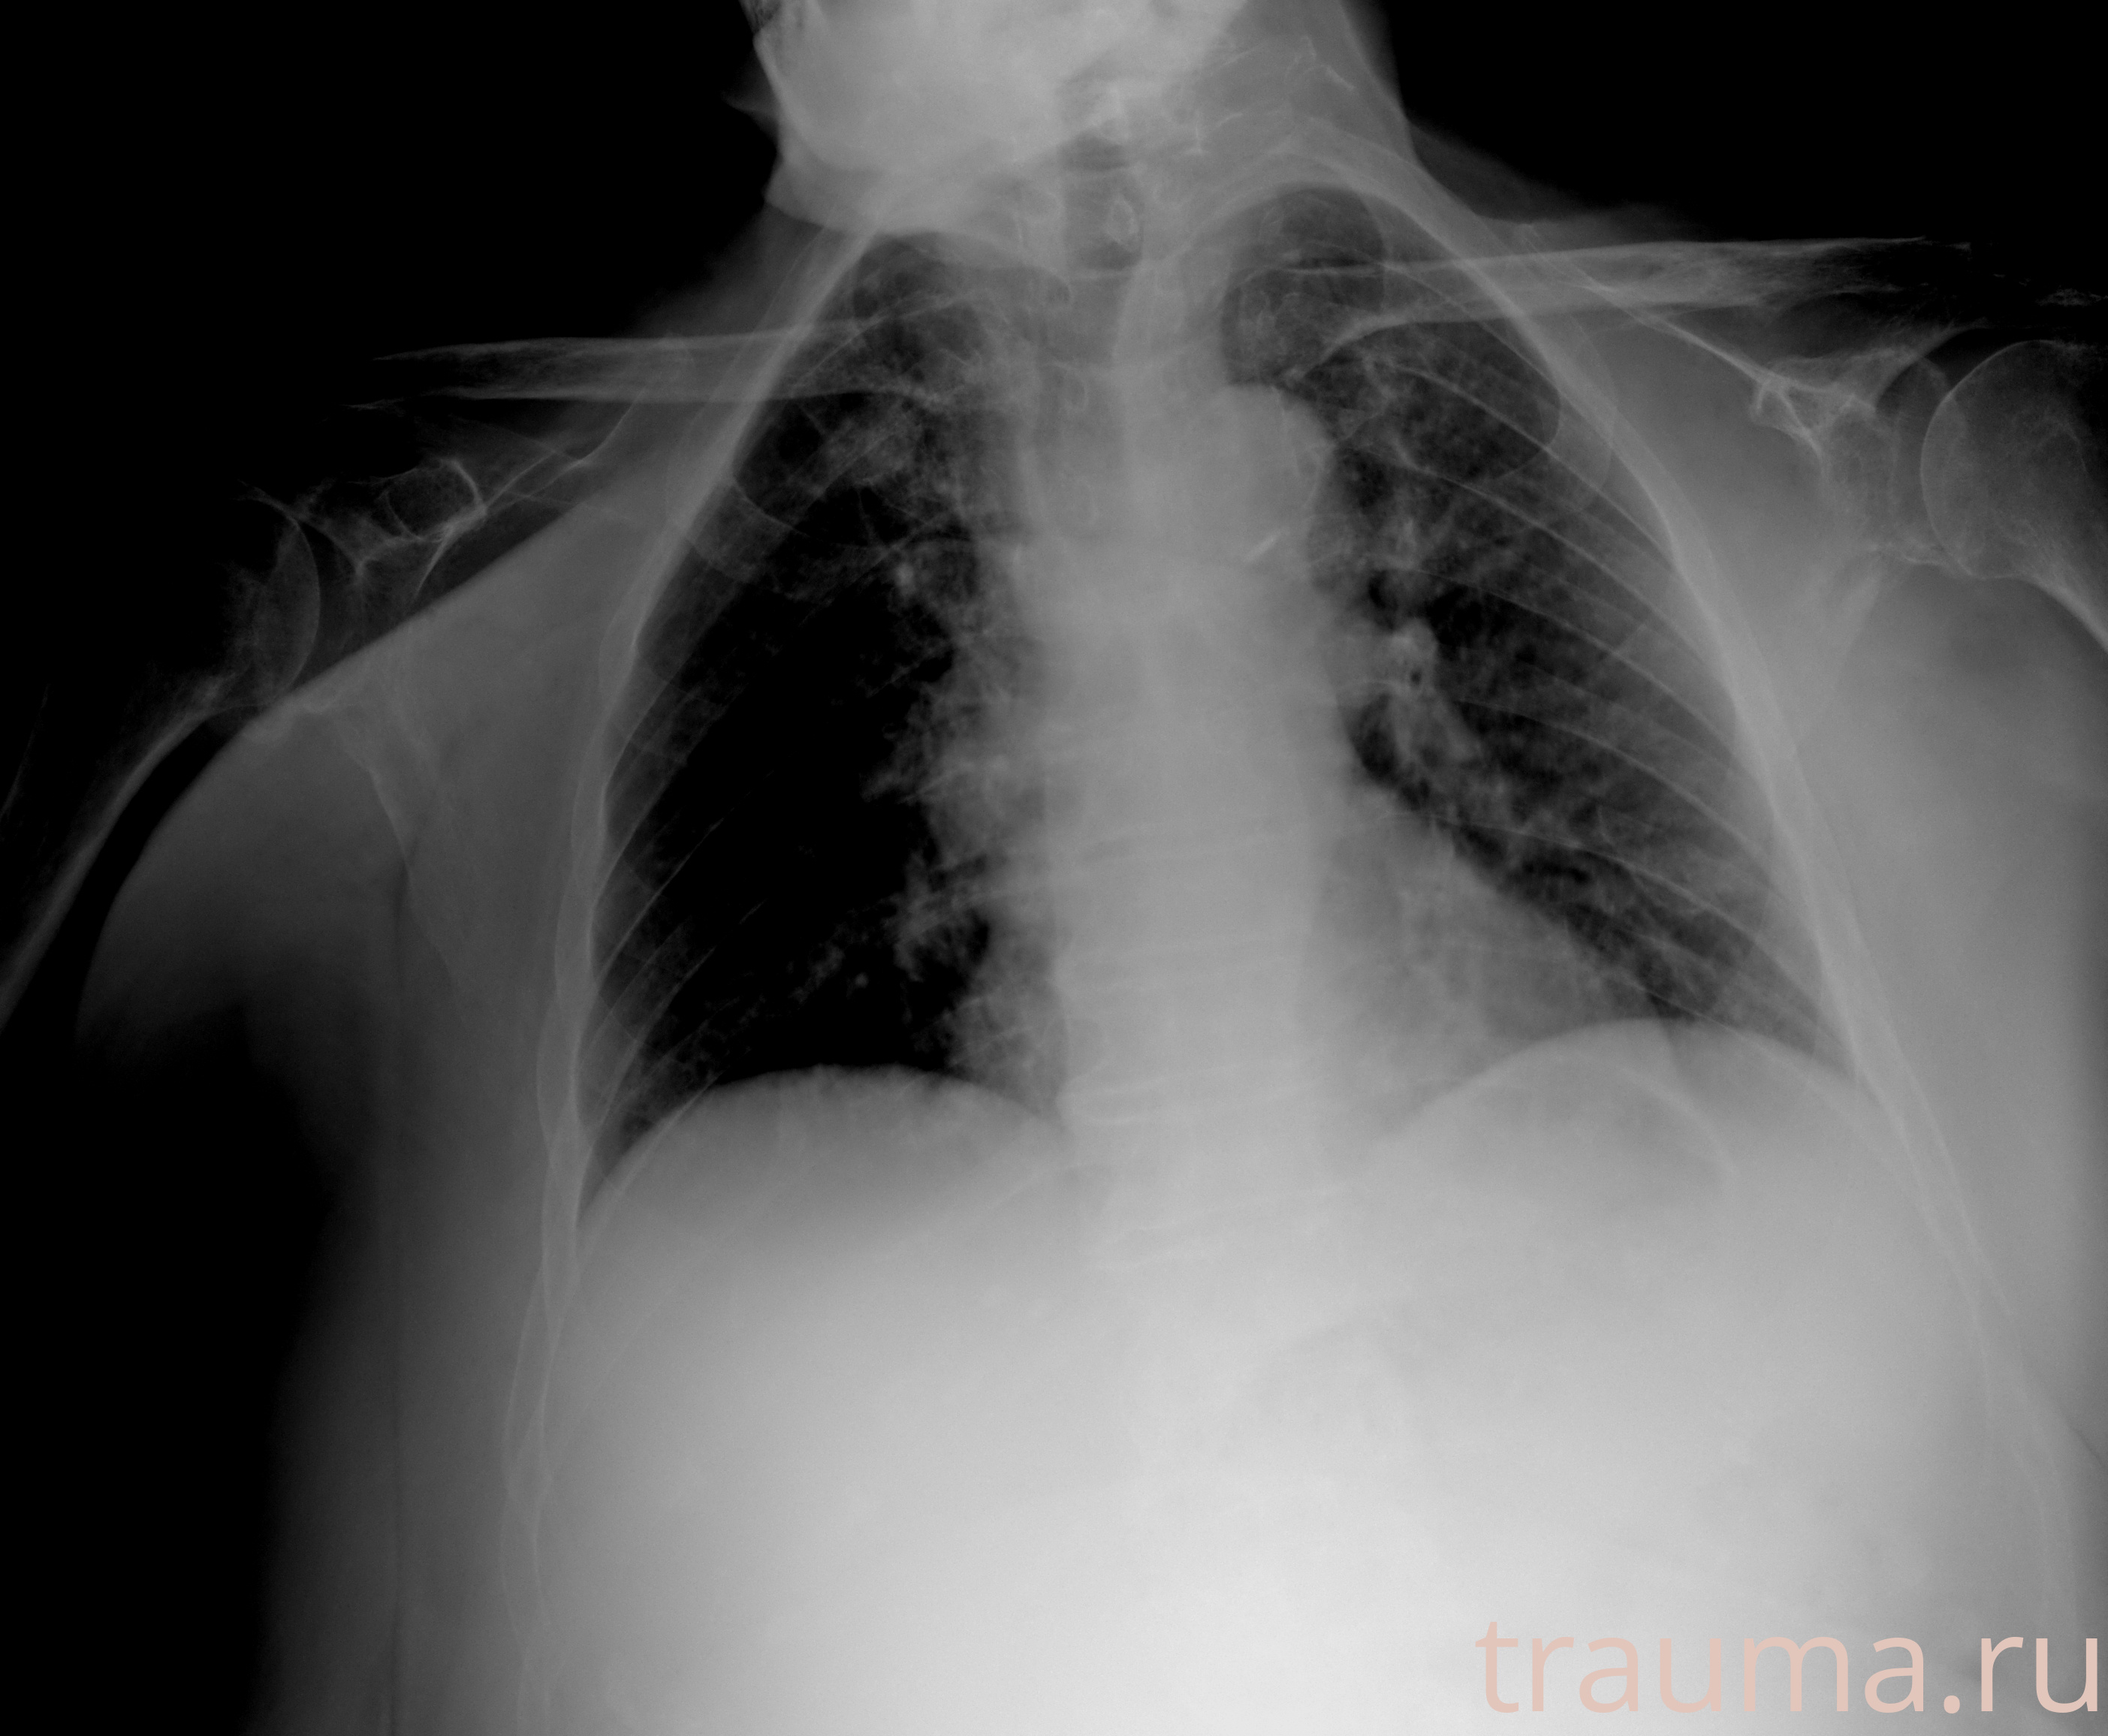

Рентгенограммы

Рентген на дому: по вашему адресу приезжает врач-рентгенолог, травматолог-ортопед с мобильным рентгеновским аппаратом, проводит диагностику травмы или заболевания, делает необходимые рентгенограммы, дает рекомендации по дальнейшему лечению. Получить качественные снимки в домашних условиях возможно благодаря уникальной методике, разработанной МосРентген Центром для института  Склифосовского

при переломе шейки бедра и пневмонии от компании МосРентген Центр - партнера Института имени Склифосовского